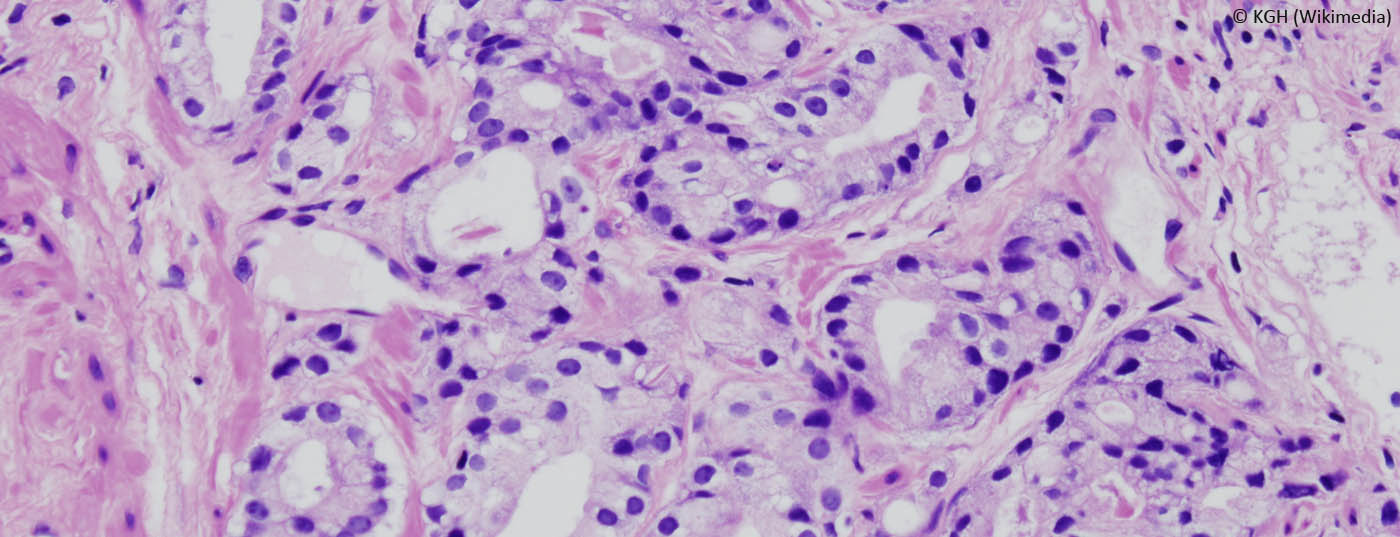

Biopsien mit hochauflösendem Ultraschall sind einer internationalen klinischen Studie zufolge bei der Diagnose von Prostatakrebs genauso effektiv wie MRT-gestützte Biopsien. Die Mikro-Ultraschall-Technologie ist zudem kostengünstiger und einfacher anzuwenden als ein MRT.